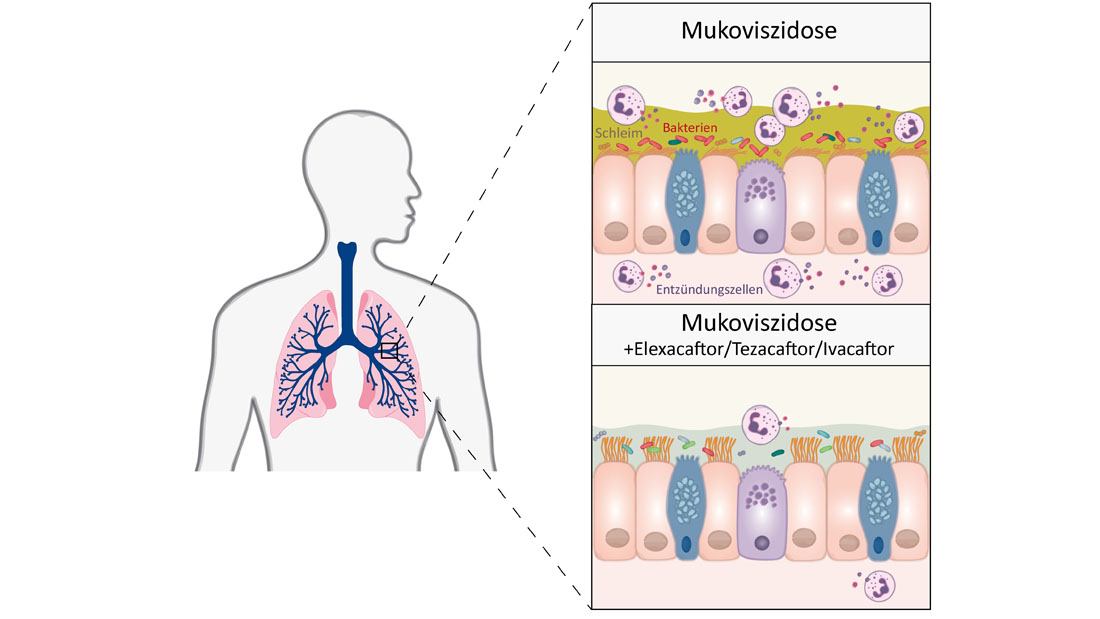

Laut Mukoviszidose e.V. sind in Deutschland mehr als 8.000 Kinder, Jugendliche und Erwachsene von der unheilbaren Erbkrankheit Mukoviszidose (Cystische Fibrose, CF) betroffen. Durch eine Störung des Salz- und Wasserhaushalts im Körper bildet sich bei Mukoviszidose-Betroffenen ein zähflüssiges Sekret, das Organe wie die Lunge und die Bauchspeicheldrüse irreparabel schädigt. Jedes Jahr werden in Deutschland etwa 150 bis 200 Kinder mit der seltenen Krankheit geboren. Die Krankheit führt zu einem fortschreitenden Verlust der Lungenfunktion und Atemnot, was die Lebenserwartung trotz verbesserter Behandlungsansätze noch immer deutlich senkt. Bereits vor zwei Jahren hatte eine Forschungsgruppe unter Leitung der Charité gezeigt, dass die Kombinationstherapie mit den drei Wirkstoffen Elexacaftor, Tezacaftor und Ivacaftor für einen großen Teil der Patientinnen und Patienten mit der Erbkrankheit Mukoviszidose wirksam ist, also die Lungenfunktion und Lebensqualität spürbar verbessert. Die Therapie kommt für knapp 90 Prozent der Mukoviszidose-Betroffenen infrage, die den häufigsten Gendefekt F508del haben.

Jetzt hat das Team um Prof. Dr. Marcus Mall, damaliger und aktueller Studienleiter, erstmals untersucht, inwiefern diese Therapie auch langfristig, das heißt über mindestens zwölf Monate hinweg, hilft. Dafür haben die Forscherinnen und Forscher das Sputum, das Atemwegssekret, genauer betrachtet. „Bei Patientinnen/Patienten mit Mukoviszidose ist der Schleim in den Atemwegen sehr zäh, weil er zu wenig Wasser enthält und die schleimbildenden Moleküle, die sogenannten Muzine, zu stark chemisch miteinander verklebt sind. Der daraus resultierende zähe Schleim verstopft die Atemwege, erschwert damit die Atmung und führt bei den Betroffenen zu einer chronischen bakteriellen Infektion und Entzündung der Lunge“, erklärt Prof. Mall, Direktor der Klinik für Pädiatrie mit Schwerpunkt Pneumologie, Immunologie und Intensivmedizin und des Christiane Herzog Mukoviszidose-Zentrums der Charité.

Die Wissenschaftlerinnen und Wissenschaftler zeigen in der aktuellen Studie, dass die Dreifachtherapie mit Elexacaftor, Tezacaftor und Ivacaftor bei Patientinnen und Patienten mit Mukoviszidose dafür sorgt, dass das Atemwegssekret weniger zäh ist und die Entzündung und die bakterielle Infektion in der Lunge abnehmen. „Und das über die gesamte Dauer der Studie von einem Jahr. Das ist deshalb so bedeutsam, weil frühere Medikationen wieder zu einem Anstieg der Bakterienlast in den Atemwegen geführt hatten“, erläutert Dr. Simon Gräber, ebenfalls von der Klinik für Pädiatrie mit Schwerpunkt Pneumologie, Immunologie und Intensivmedizin der Charité und Co-Leiter der Studie. An dieser nahmen 79 Jugendliche und Erwachsene mit Mukoviszidose und einer chronischen Lungenerkrankung teil.